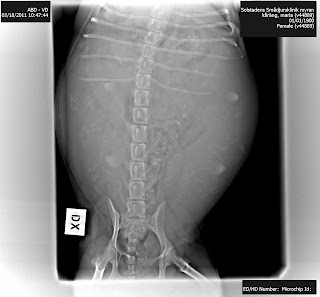

Bolla valpade på dag 61 och röntgenbilden är tagen på dag 59. Valparnas skelett är väl mineraliserade och syns tydligt.

Den här bilden är Zenias. Hur många skelett finner du här?

Jag kan avslöja att jag och tjejen som avläste plåtarna inte var överens. Sen kom veterinären, hon ökade antalet med en och jag var fortfarande inte överens. Jag ville ha det till sex stycken valpar i lilla Myrnas mage - och jag fick rätt :) Kan du hitta dem?